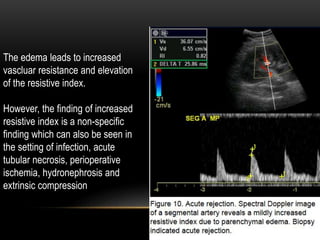

The edema leads to increased

vascluar resistance and elevation

of the resistive index.

However, the finding of increased

resistive index is a non-specific

finding which can also be seen in

the setting of infection, acute

tubular necrosis, perioperative

ischemia, hydronephrosis and

extrinsic compression